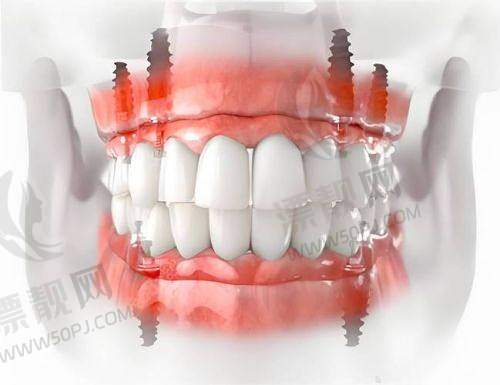

| 全口种植 | ¥8W~15W | ¥9999起 | 多次可选,适合中老年 |

在医院整体档次这块,德韩口腔属于标准的“中高端口腔机构”,在连锁体系中算非凡学霸级别:用的是德国卡瓦CT,数字化导板种植技术、全景X光、3D扫描这些全配齐,而且医生必须经历层层筛选,临床经验10年以上的才有资格加入主诊。